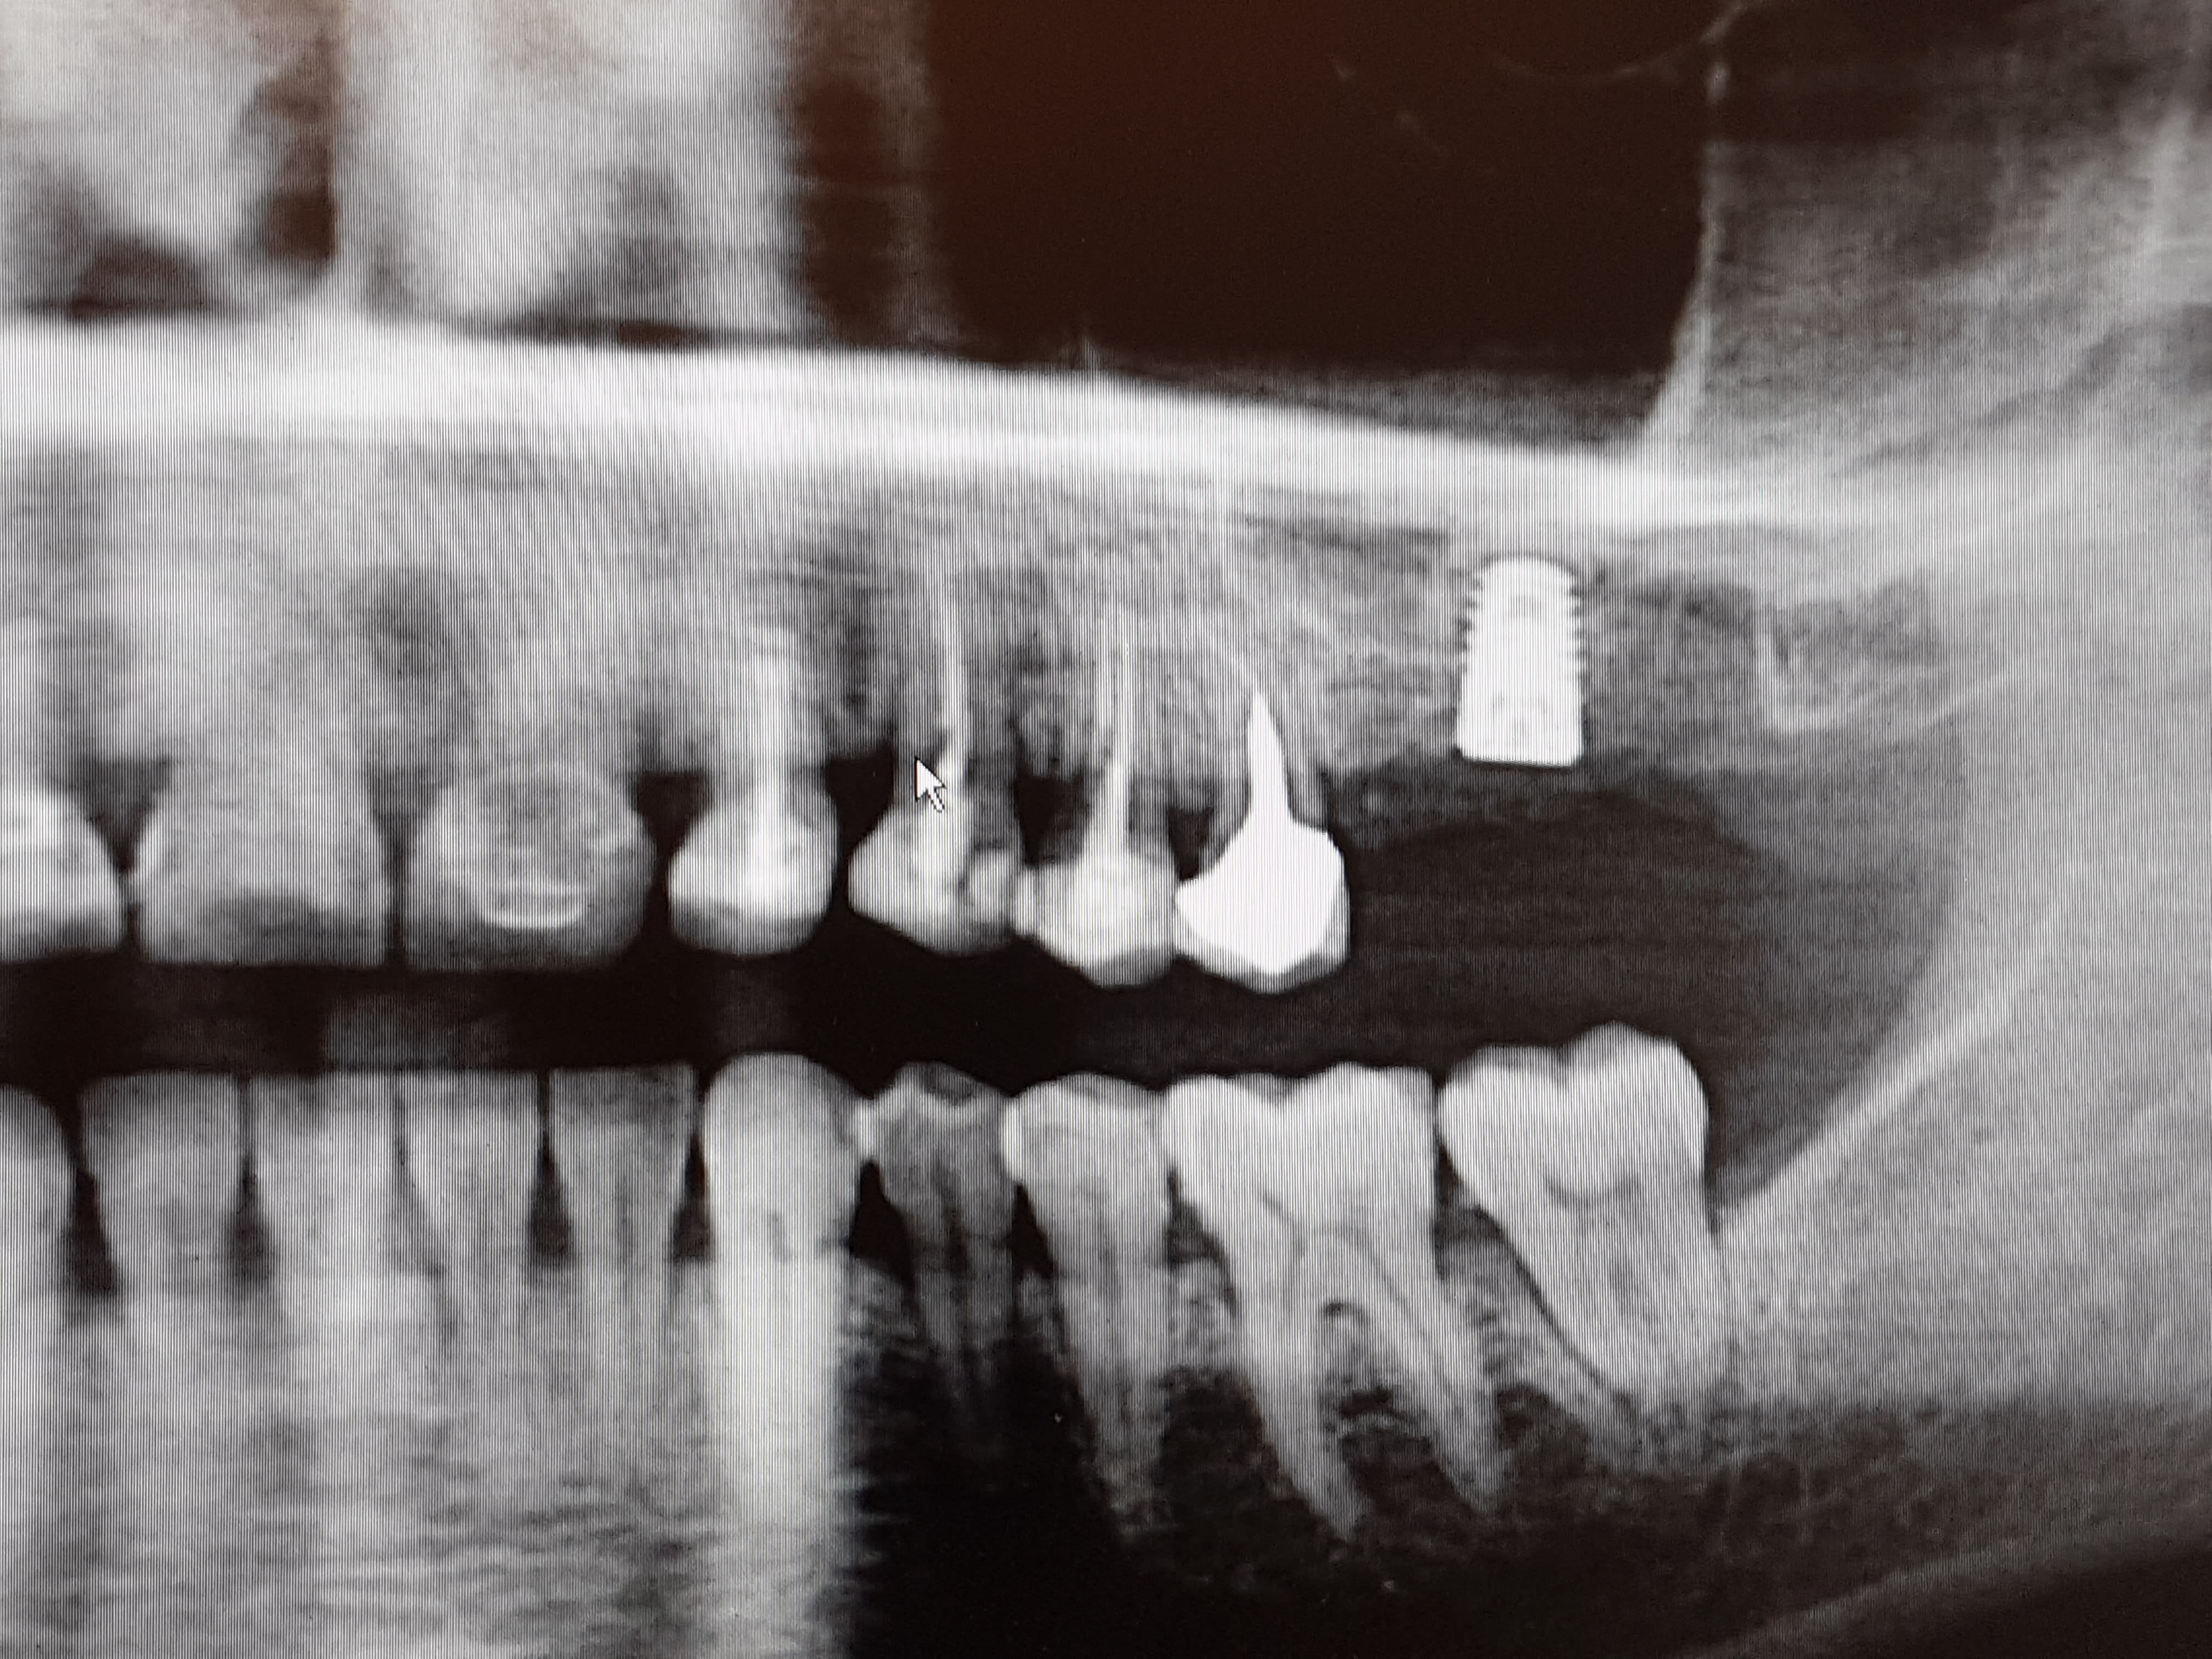

Un autre exemple de l'utilisation des versah. Cas d'EII sur 26, Forage dans le septum et osseodensification. Souleve' de sinus de 5mm mais sans comblement. Controle à 7 jours, aucune douleur post op.

20171018 094131 hjcxwj - Eugenol

20171018 094139 iocwui - Eugenol

20171018 095402 zrdzxf - Eugenol